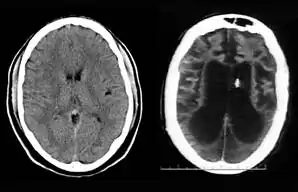

On August 10, 2001, on remand from the Florida Second District Court of Appeal, Judge Greer heard a motion from the Schindlers claiming that new medical treatment could restore sufficient cognitive ability such that Terri Schiavo herself would be able to decide to continue life-prolonging measures. The court also heard motions from the Schindlers to remove the guardian (Michael Schiavo) and to require Judge Greer to recuse himself. Judge Greer denied the motions and the Schindlers appealed to the Second District Court of Appeals. On October 17, 2001, the Court of Appeal affirmed the denials of the motions to remove and recuse. The Court of Appeals acknowledged that their opinion misled the trial court, and they remanded the question of Terri Schiavo's wishes back to the trial court and required an evidentiary hearing to be held. The court specified that five board certified neurologists were to testify. The Schindlers were allowed to choose two doctors to present findings at an evidentiary hearing while Schiavo could introduce two rebuttal experts. Finally, the trial court itself would appoint a new independent physician to examine and evaluate Terri Schiavo's condition. (These decisions, all published in a single order by the Florida Second District Court of Appeal,[33] came to be known by the court as Schiavo III in its later rulings.) In October 2002, on remand by the Second District Court of Appeal, an evidentiary hearing was held in Judge Greer's court to determine whether new therapy treatments could help Terri Schiavo restore any cognitive function. In preparation for the trial, a new computed axial tomography scan (CAT scan) was performed, which showed severe cerebral atrophy. An EEG showed no measurable brain activity. The five physicians chosen were William Maxfield, a radiologist, and four neurologists: William Hammesfahr, Ronald Cranford, Melvin Greer and Peter Bambakidis.[34]

The five doctors examined Terri Schiavo's medical records, brain scans, the videos, and Terri herself. Cranford, Greer, and Bambakidis testified that Terri Schiavo was in a persistent vegetative state. Drs. Maxfield and Hammesfahr testified that she was in a minimally conscious state. As part of the court-ordered medical exam, six hours of video of Terri Schiavo were taped and filed at the Pinellas County courthouse. The tape included Terri Schiavo with her mother and neurologist William Hammesfahr. The entire tape was viewed by Judge Greer, who wrote, Terri "clearly does not consistently respond to her mother." From that six hours of video, the Schindlers and their supporters produced six video clips intended to support their case, totaling less than six minutes, and released those clips to public websites.[1] Judge Greer ruled that Terri Schiavo was in a PVS, and was beyond hope of significant improvement. The trial court order was particularly critical of Hammesfahr's testimony, which claimed positive results in similar cases by use of Vasodilation therapy, the success of which is unsupported in the medical literature.[35] This ruling was later affirmed by Florida's Second District Court of Appeal, which stated that "this court has closely examined all of the evidence in the record," and "we have ... carefully observed the video tapes in their entirety." The court concluded that "if we were called upon to review the guardianship court's decision de novo, we would still affirm it." This decision by the Second District Court of Appeals[36] came to be known as Schiavo IV in later rulings.

After her death, Schiavo's body was taken to the Office of the District 6 Medical Examiner for Pinellas and Pasco counties, based in Largo, Florida. The autopsy occurred on April 1, 2005. It revealed extensive brain damage. The manner of death was certified as "undetermined." The autopsy was led by Chief Medical Examiner Jon R. Thogmartin. In addition to consultation with a neuropathologist (Stephen J. Nelson), Thogmartin also arranged for specialized cardiac and genetic examinations to be made. The official autopsy report[28] was released on June 15, 2005. In addition to studying Terri Schiavo's remains, Thogmartin scoured court, medical and other records and interviewed her family members, doctors and other relevant parties. Examination of Schiavo's nervous system by neuropathologist Stephen J. Nelson, revealed extensive injury. The brain itself weighed only 615 g (21.7 oz), only half the weight expected for a female of her age, height, and weight, an effect caused by the loss of a massive number of neurons. Microscopic examination revealed extensive damage to nearly all brain regions, including the cerebral cortex, the thalamus, the basal ganglia, the hippocampus, the cerebellum, and the midbrain. The neuropathologic changes in her brain were precisely of the type seen in patients who enter a PVS following cardiac arrest. Throughout the cerebral cortex, the large pyramidal neurons that comprise some 70% of cortical cells – critical to the functioning of the cortex – were completely lost. The pattern of damage to the cortex, with injury tending to worsen from the front of the cortex to the back, was also typical. There was marked damage to important relay circuits deep in the brain (the thalamus) – another common pathologic finding in cases of PVS. The damage was, in the words of Thogmartin, "irreversible, and no amount of therapy or treatment would have regenerated the massive loss of neurons."[68]